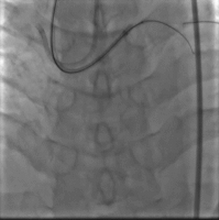

取0.014" Runthrough NS导丝通过病变送入高位钝缘支远端(图4),送入Atlantis SR血管内超声导管至左主干远段,未见明确前降支开口影像,0.014" Sion导丝未能通过前降支近段支架内闭塞病变处,换用0.014" ConquestPro导丝成功通过前降支近段支架内闭塞病变送至前降支中段(图5、6),换入0.014" Sion导丝至前降支远端,Sprinter Legend 2.5×15 mm球囊锚定导丝后,再以该球囊成功通过闭塞病变,反复以10~12 atm×5 s扩张(图7)。复查造影显示前降支恢复TIMI 3级血流,前降支近段处残余狭窄50%,中段局限性狭窄70%(图8)。Sprinter Legend 2.5×15 mm球囊以6 atm×8 s扩张前降支中段病变后,送入IVUS导管至前降支中段连续自动回撤示前降支中段心肌桥征象,近段弥漫性纤维斑块形成。植入Buma 3.5×25 mm雷帕霉素药物支架以10 atm×8 s扩张释放(图9),稍前送该支架球囊至两支架交界处以10 atm×8 s再次扩张塑形。行IVUS检查左主干内支架贴壁不良。取Quantum 4.5×12 mm高压球囊至左主干支架内以14~20 atm×8 s扩张塑形(图11),复查造影示支架扩张满意,残余狭窄<30%,血流TIMI 3级,回旋支血流未受影响(图12)。复查血管内超声示支架扩张满意,贴壁良好,支架两端无夹层征象。

图4